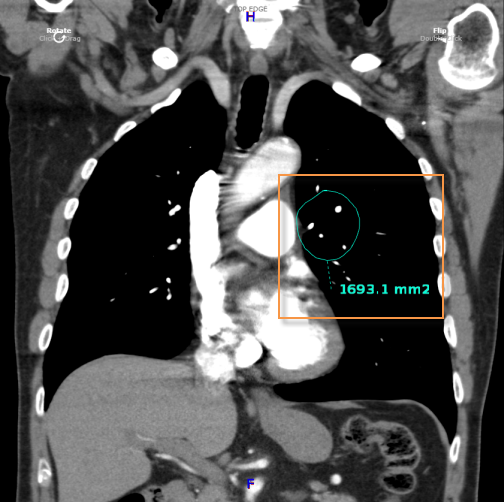

To obtain a free region measurement:

Select the

Free Region  icon

icon

Click on the region of interest

Drag on the mouse to encircle the area

Release the mouse button

To move the whole free region, select the upper

grab point  . To

extend areas of a free region, click on the desired area to reveal 3 grab

points. Selecting one of these grab points will extend the free

region to include a specific area.

. To

extend areas of a free region, click on the desired area to reveal 3 grab

points. Selecting one of these grab points will extend the free

region to include a specific area.